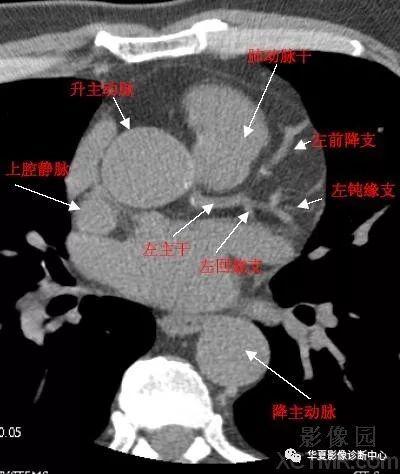

心脏冠状动脉ct解剖中文详细标注(图文)

ct和mri如何看正常及异常冠状动脉,高清图谱请收好!

冠状动脉CT解剖